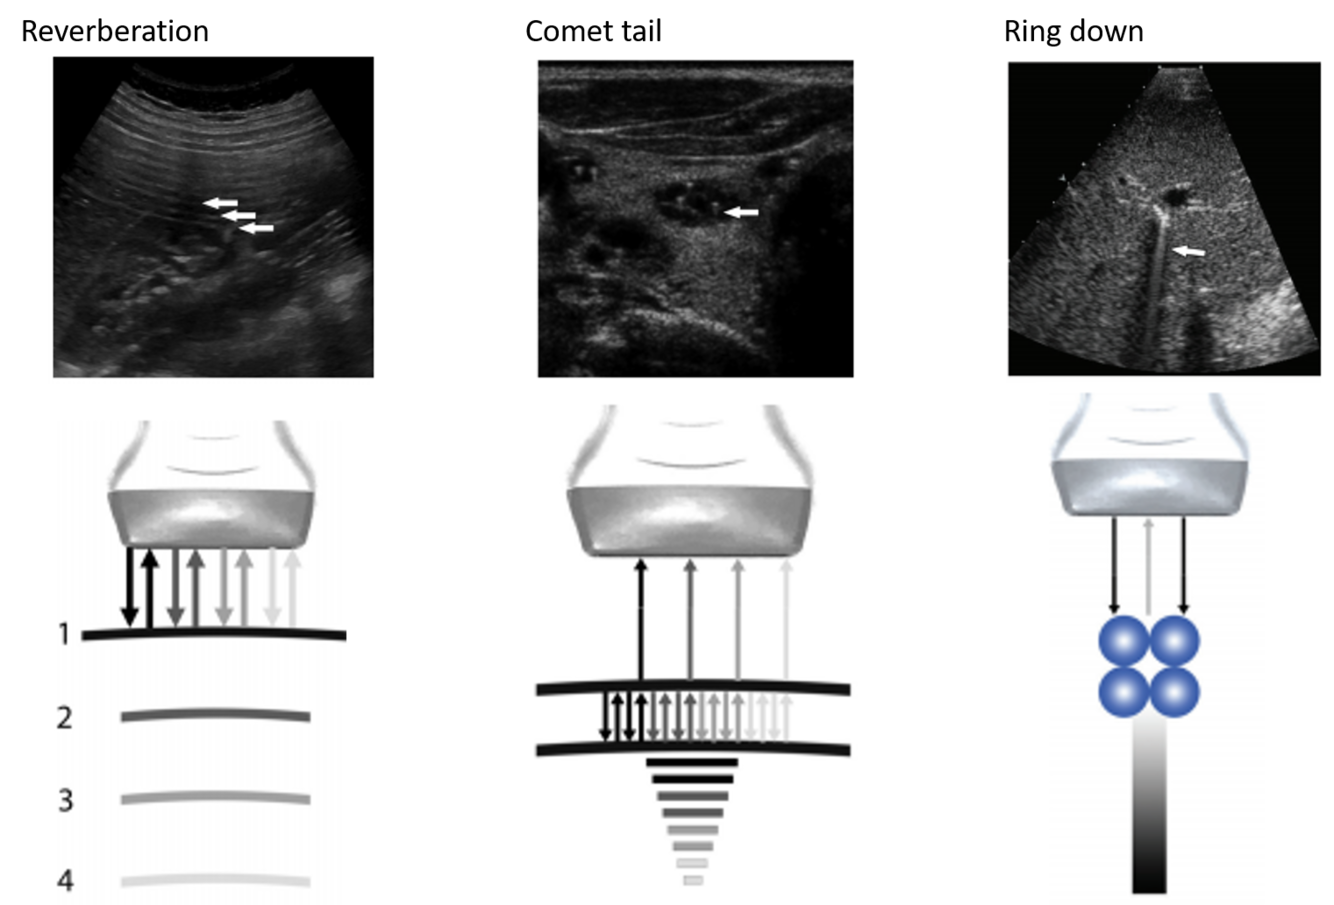

The artifact shown is reverberation caused by back and forth reflection of the ultrasound beam between 2 closely spaced interfaces. These reverberation echoes appear as multiple equally spaced lines, which decrease in intensity with increasing depth. This artifact is often caused by highly reflective interfaces, e.g., metallic objects or calcification in tissues.

reverberation artifact:

multiple equidistance echoes

why do you get a tapering triangle in comet tail artifact?

comet tail artifact is a form of reverberation, but the two parallel highly reflective surfaces are closer together –> sequential echoes are closely spaced

spce between reflectors may be < SPL (minimal distance needed for axial res)

Reason you see a triangle and not a square: later echoes get attenuated and have decreased amplitutde. Decreased amplitude is manifested on the displayu as decreased width. So you get a tapering triangle

ring down artifact

sound wave encounters fluid trapped between a tetrahedron of air bubbles. The vibrations create a nearly continuous sound wave transmitted back towards the probe